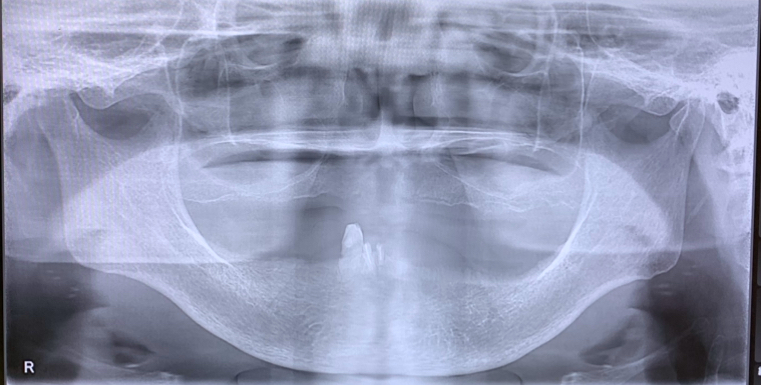

Title ” 総義歯の患者様のインプラント症例”

2024年暮れ、義歯(入れ歯)の痛みで

食事ができない患者様(75歳)が来院されました。

診察をしたところ、下顎の骨の痩せ方が著しく

義歯(入れ歯)が安定しにくいため

固定式のインプラントを提案しました。

固定式のインプラントをすることで、

上顎も外れない安定した総義歯になるということです。

下顎インプラントを4本埋入した状態

インプラントが4本埋入した下顎模型

下顎インプラント模型に仮歯が入っている状態

上部構造が入っている状態(下顎パノラマ写真)

下顎口腔内に最終補綴物(被せ物)が入っている状態

上顎総義歯&下顎インプラントブリッジが入っている状態(口腔内写真)